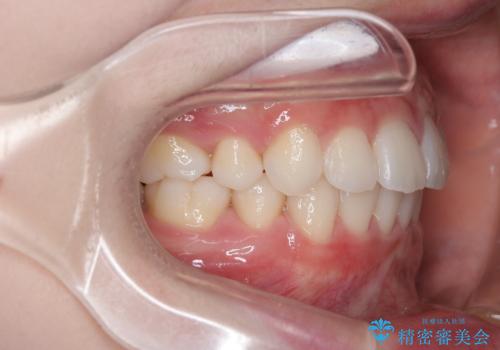

【審美装置】歯を抜いてEラインをきれいに

- 出っ歯を主訴に来院されました。今回は4番の歯を4本抜歯をし、ワイヤー矯正にて治療しました。

抜歯矯正のため2年を予定してましたが、予定よりも早く終わることができました。また口元も下がり、かみ合わせも改善しました。